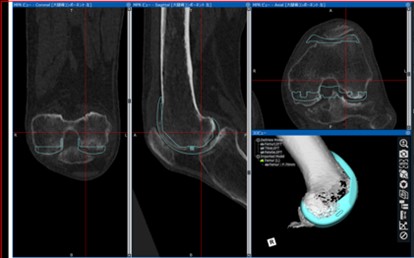

最近はtrabecular metalという構造を持った人工足関節で骨セメントを使用しなくても手術ができるケースが増えています。